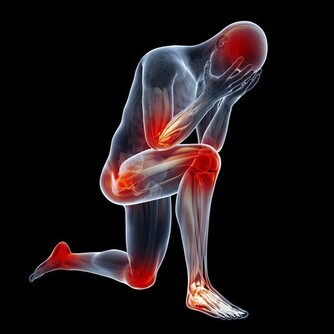

3. 你的肋骨疼得厲害

食道裂孔疝是一種胃的一部分通過食管裂孔進入食道的疾病,可導致反复打嗝。就其本身而言,裂孔疝不是緊急情況,但它可能讓你非常不舒服。當疝氣切斷腹部其他部位的血液供應時,疝氣也會變得“絞亂”。這時候需要緊急手術,如果不及時治療後果可能是致命的。